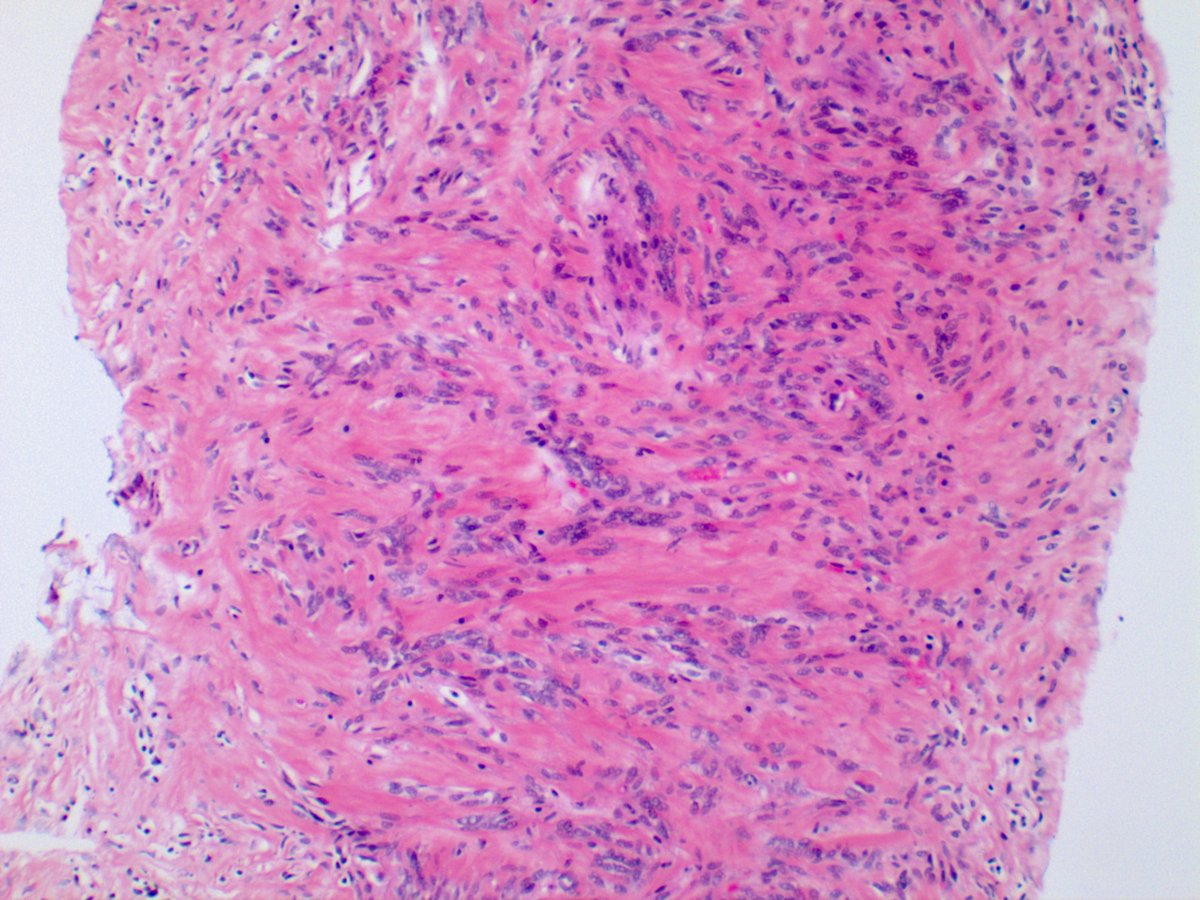

Biopsy shows the so-called "patternless pattern" of spindle cells with a hemangiopericytic growth pattern. These tumors are thought to arise from which of the following cell types?

Mesenchymal, probably fibroblastic; and yes, you guessed it...this is a Solitary Fibrous Tumor (STF). SFTs can be found almost anywhere but intra-thoracic is the most common location. Pleura-based is the most common location within the thoracic cavity. Clinching stain is STAT6